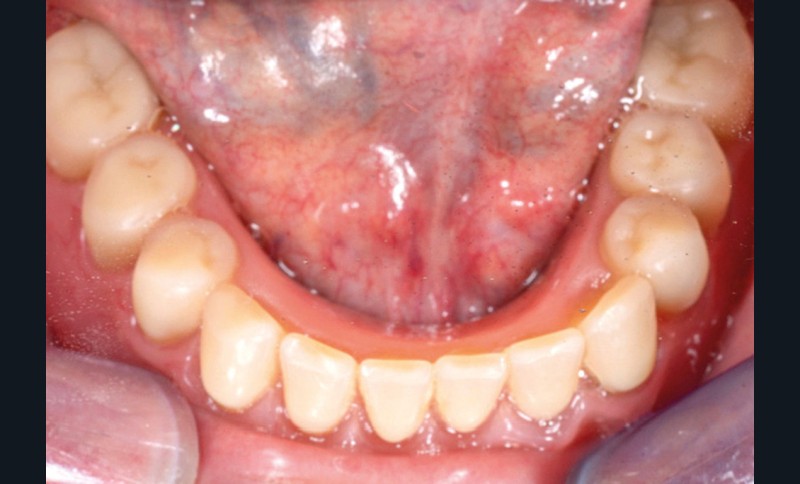

Dans le cas clinique présenté dans cet article, le patient édenté total bimaxillaire se plaint d’une gêne importante et d’une insatisfaction de son sourire en lien avec un plan d’occlusion prothétique inadapté (fig. 1 et 2).